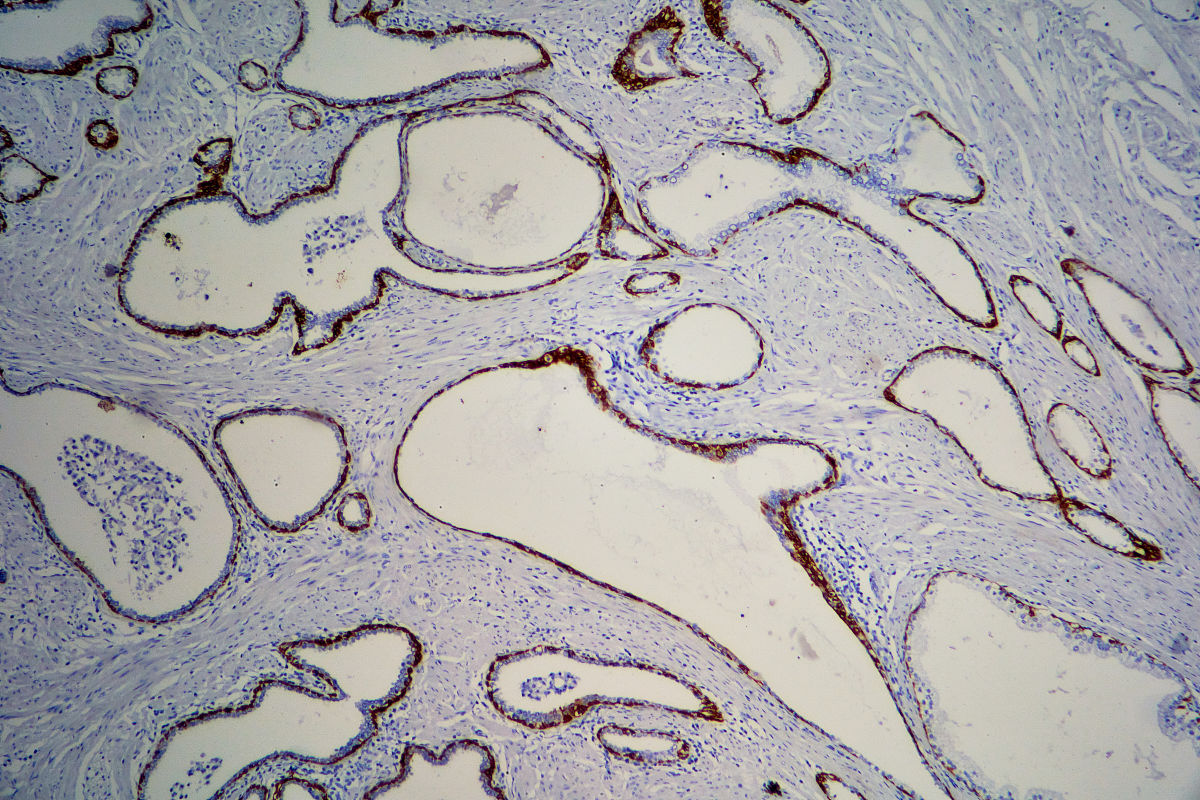

石蜡切片法中脱水后将直接样品放入加热的石蜡中使其充分浸透。

然后将石蜡冷却并固化,形成一个坚固的块状样品。接着,使用旋转式微浸机或手动旋转式微浸机将样品切成薄片,通常厚度为4-7微米。切片后,可以用染色剂染色并进行显微镜观察和分析。石蜡切片法可用于组织学和病理学研究,也可用于其他领域的样品制备和分析。